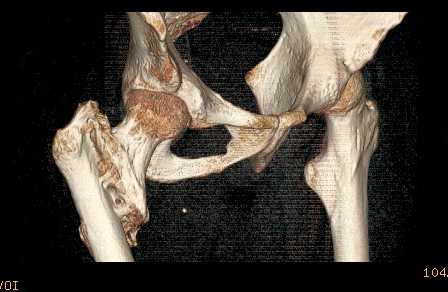

Доброго времени суток, уважаемые коллеги! Больному 45 лет. Лечили в сельской больнице на скелетном вытяжении 6 нед. по поводу межвертельного перелома бедренной кости с последующим наложением кокситной повязки еще на 2 мес.

С момента травмы прошло 5 месяцев, ходит с костылями без нагрузки, контрактуры в коленном и в тазобедренном суставах. Снимки во вложении. У нас мнения разделились. Показанием для открытого остеосинтеза мы считаем неустраненное ротационное смешение дистального фрагмента, которое может привести к нарушению биомеханики в тазобедренном суставе с последющими вытекающими последствиями. ЭОП на сегодняшний день недоступен нам, а остеосинтез угловыми пластинами, что можно попытаться, имеет определенный риск. Как быть? Начать разработку в суставах и активизировать больного, что не было сделано до этого, или всё-таки оперировать? Будем рады Вашим советам.

Никаких особенных проблем не видно, оперировать не видно, ради чего. Большого ротационного смещения нет, тазобедренный сустав - шаровидный, такие смещения прощает. Укорочение есть, но небольшое.

A что Вы думаете по поводу консолидации? Если имеется, почему до сих пор ходит с костылями? Если нет - о какой разработке суставов идет речь? Судя по рентгенограмме - не срослось. По КТ - ткань розового цвета между отломками такая же, как та, что покрывает головку. Тоже вроде не срослось. Мужику 45 лет. Конечно оперировать.